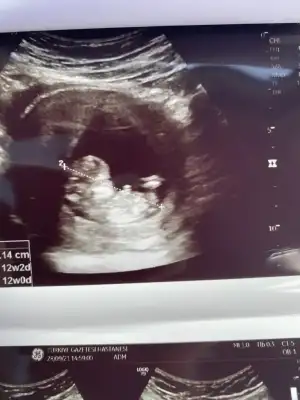

Erkek sankiKızlar 11+3 deyiz bize de tahminde bulunur musunuz

Kız gibi sankiKizlar benim minigimede bakarmisiniz 12+4deyizIkra meyra

Emin olamadım başka USG varsa paylaşın 11 12 13 haftalar olmalıMerhaba rica etsem banada yorum yaparmısınızIkra meyra

Net değil USG başka USG varsa paylaşın emin olamadım kız olabilir sanki SankiKizlar bizde 12+4Bi baksaniz cok mutlu olurumm